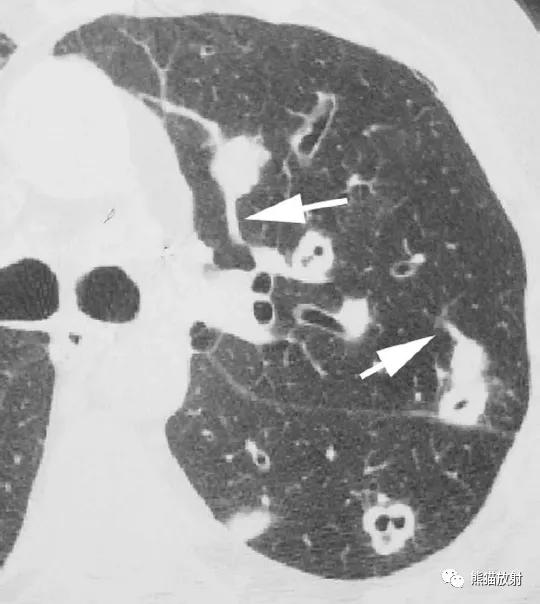

横断面CT图像上结节影常可见血管影与之相连(“供血血管征”)(图)。由于致病病原体的不同,结节常在不同的时期形成空洞,导致实性结节和结节伴大小不等的空洞同时存在。

↑ 脓毒性肺栓塞 Septic embolism

40岁男性,发热,静脉注射*品毒**史。CT显示左肺多发空洞性结节,不同的血管与结节相连。血培养金黄色葡萄球菌阳性。